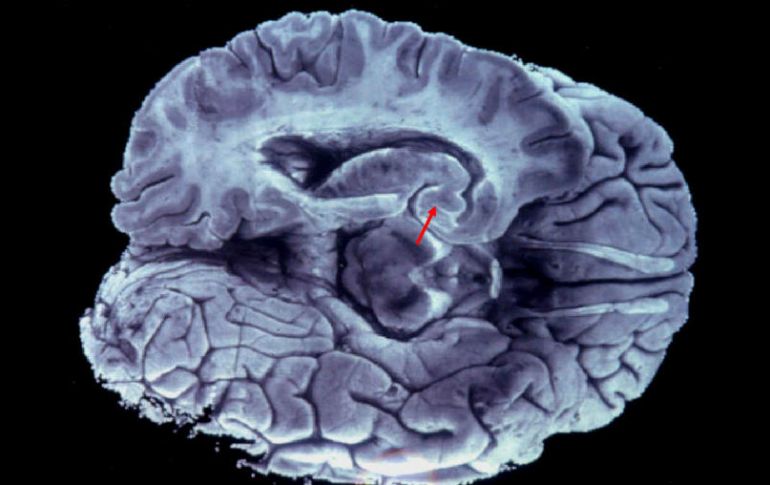

El órgano está dividido en dos hemisferios y para actuar en común se conectan mediante fibras nerviosas. EFE / ARCHIVO

El jefe del Laboratorio de Neurociencias de la Facultad de Psicología de la Universidad Nacional Autónoma de México (UNAM) explicó que el cerebro está dividido en dos hemisferios y para actuar en común se conectan mediante fibras nerviosas, que de llegarse a desconectar es como si el cuerpo estuviera ocupado por dos individuos.

Señaló que existen casos de personas que nacen sin las fibras nerviosas, también llamadas cuerpo calloso, y otros donde se ha tenido que cortar ese filamento por alguna enfermedad.